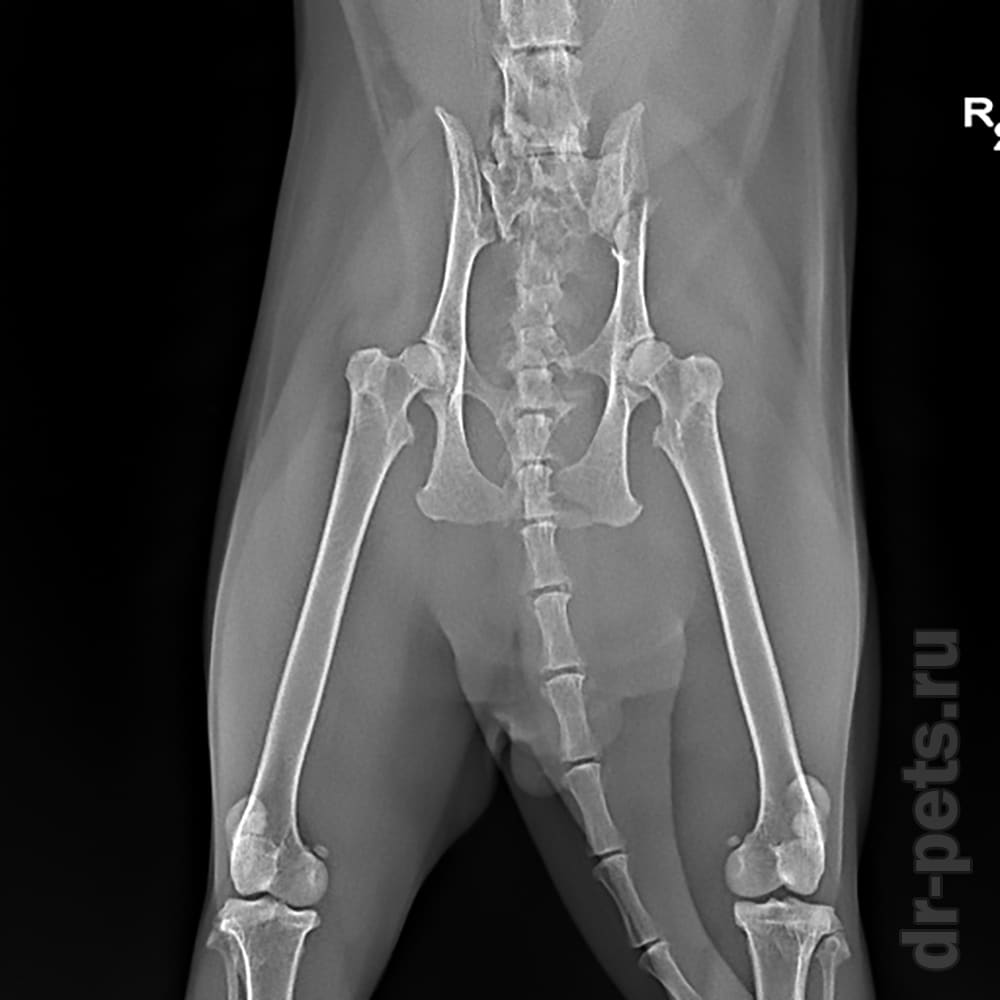

Рентгеновские снимки анатомии собак: строение и здоровье